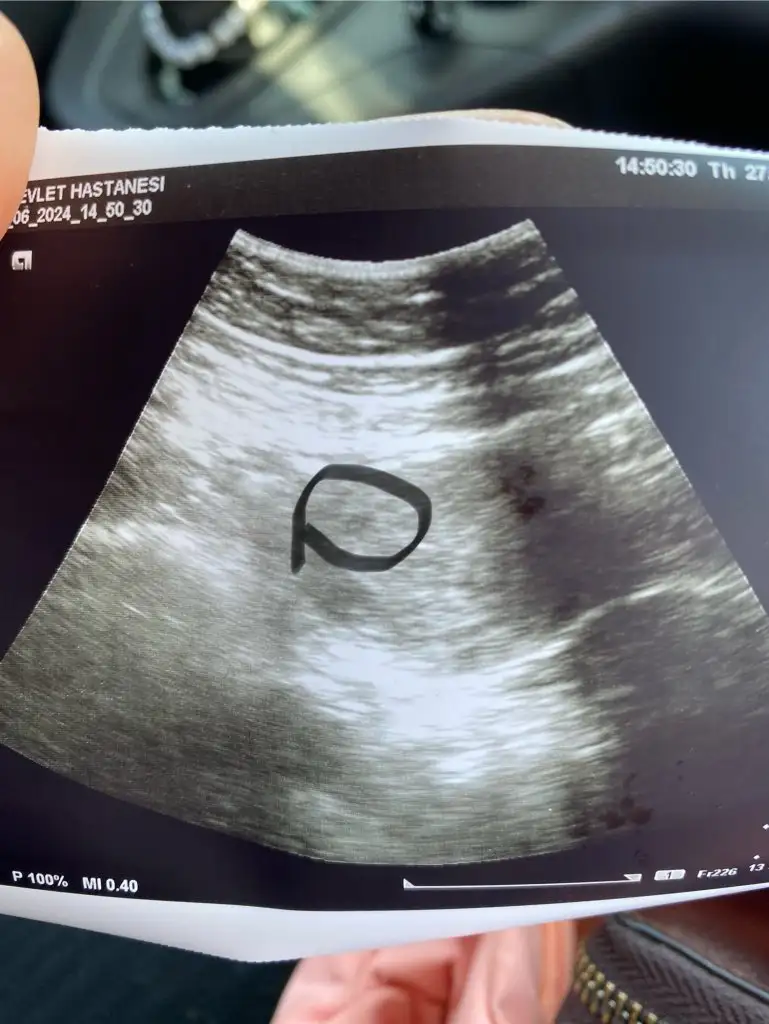

Keseyi görürsün. Bebek 7-8. Haftalarda gözükebiliyor kalp atışıyla. Keseden 10 gün sonra zaten bebek ve kalp atışı için çağırıyor doktorlarMerhabalar beta değerlerim olması gerektiği gibi ilerliyor çok şükür 25 inde kan verdiğimde 2992 çıktı betam şimdi 27 sinde doktor randevum var sizce bebek gözükür mü şuan adet tarihime göre 5+3 teyim 27 sinde de büyük ihtimal 6000 falan olur hcg çok heyecanlıyım ilk bebeğim ve beklenmedik anda hamile kaldım hiç tecrübem yok

Keseyi görürsünüz ama bebek için erken 1 hafta 10 gün sonra görürsünüzMerhabalar beta değerlerim olması gerektiği gibi ilerliyor çok şükür 25 inde kan verdiğimde 2992 çıktı betam şimdi 27 sinde doktor randevum var sizce bebek gözükür mü şuan adet tarihime göre 5+3 teyim 27 sinde de büyük ihtimal 6000 falan olur hcg çok heyecanlıyım ilk bebeğim ve beklenmedik anda hamile kaldım hiç tecrübem yok

Ben bugün gittim minik gözüktü kese ama daha küçük haftaya tekrar gel dedi üç hafta boyunca gidcem her hafta :) nokta kadar ordan büyümeye başlicak dedi doktor hayırlısı olsun hepimiz içinn alttan baktırmadım ordan bakılsa daha net çıkardı ama haftaya tekrar gidicez daha da büyür dediiiicanım benzer beta ile 5+4’te bebeği, 6+2’de de kalp atışını görmüştümumarım sen de görebilirsin.

Noldu son durum nedirr bende bugün 5+3teyim dün kese göründü bebek yok bugün tekrar gidicemMerhabalar beta değerlerim olması gerektiği gibi ilerliyor çok şükür 25 inde kan verdiğimde 2992 çıktı betam şimdi 27 sinde doktor randevum var sizce bebek gözükür mü şuan adet tarihime göre 5+3 teyim 27 sinde de büyük ihtimal 6000 falan olur hcg çok heyecanlıyım ilk bebeğim ve beklenmedik anda hamile kaldım hiç tecrübem yok